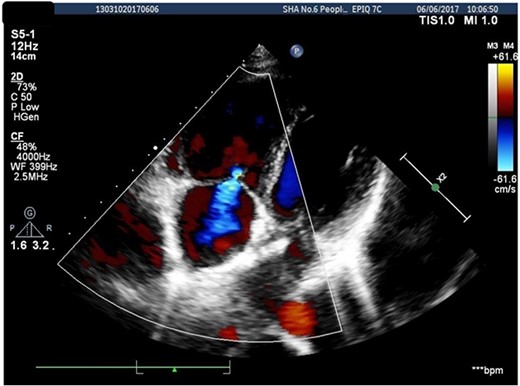

A 26-years-old woman comes to the hospital because of a 1-week history of fatigue. She has no history of serious illness and cardiovascular examination history. She can do light to moderate physical activity without developing dyspnea. Vital signs are within normal limits. Cardiac auscultation shows a heart murmur at the second intercostal space on the left sternal border and a wide-split S2 that does not change with respiration. Physical examination shows no bluish-colored lips or digital clubbing. The transthoracic echocardiography indicated atrial septal defect (Type II, diameter 25 mm); left-to-right bidirectional shunt, severe pulmonary hypertension (estimate PAP: 114 mmHg); right atrium and ventricular dilatation with severe tricuspid regurgitation (Fig. 1). Blood gas analysis showed: PH: 7.36, PaO2: 77.2 mmHg and PaCO2: 36.1 mmHg. The electrocardiogram was normal. Chest radiograph demonstrated pulmonary artery segment bulging suggesting severe PH. Right-heart catheter verified severe PH (PAP: 112 mmHg). Therefore, repair or closure of the ASD would be a high risk of developing a probable surge of pulmonary artery pressure. After serious consideration, we decided to treat her with a manual fenestrated closure device. Under general anesthesia and transesophageal echocardiography (TEE) guidance, the patient has inserted a handmade fenestrated Amplatzer Septal Occluder (reserved hole 5 mm, Abbott, St. Paul, MN, USA; Fig 2) through the right femoral vein, occlusion of the occluder in advance. After the device was released, TEE showed a slight left-to-right shunt. After the procedure, the patient’s oxygen saturation was 100%. On the second day after surgery, this patient was discharged. Echocardiography was performed in the second month and sixth month since discharge, and the PAP was 68 and 34 mmHg, respectively. Meanwhile, tricuspid regurgitation was reduced to mild. The right atrium and right ventricle size also decreased compared with preoperative. Therefore, the patient’s PH was reversible since the PAP decreased significantly after the first-step procedure. Thus, after careful evaluation, we take the second stage of the procedure to re-plug the 5-mm reserved hole by using the Amplatzer Septal Occluder (Abbott, St. Paul, MN) to eliminate the shunt Fig. 3). The surgery was successful and the patient was discharged the next day.